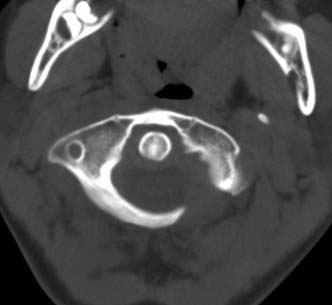

标题: PED0678:男,10岁,寰枢椎平扫。 [打印本页]

标题: PED0678:男,10岁,寰枢椎平扫。

患者在校与同龄孩子打闹后(据家长说被拳击中颈部)出现颈部不适30分钟后入院检查,来时脖子歪斜。请大家看看枢椎齿状突及寰枢关节有问题吗?(3mm层厚断层扫描)。